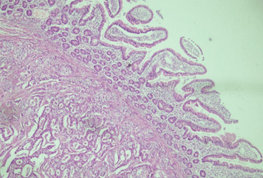

A growing papillary tumor with remarkable fibrosis and lymphocytic infiltration is clearly seen (Courtesy Dr. V. Penopoulos)